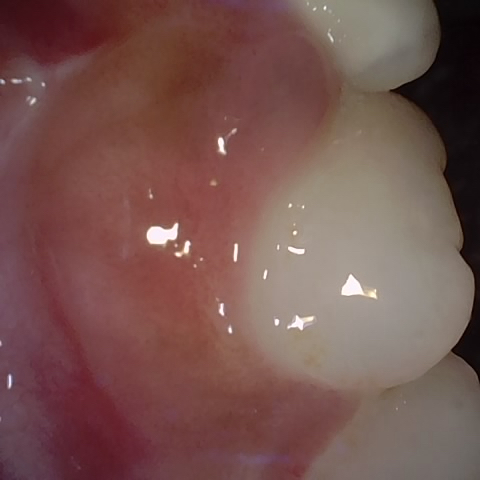

Annotated as "Good"